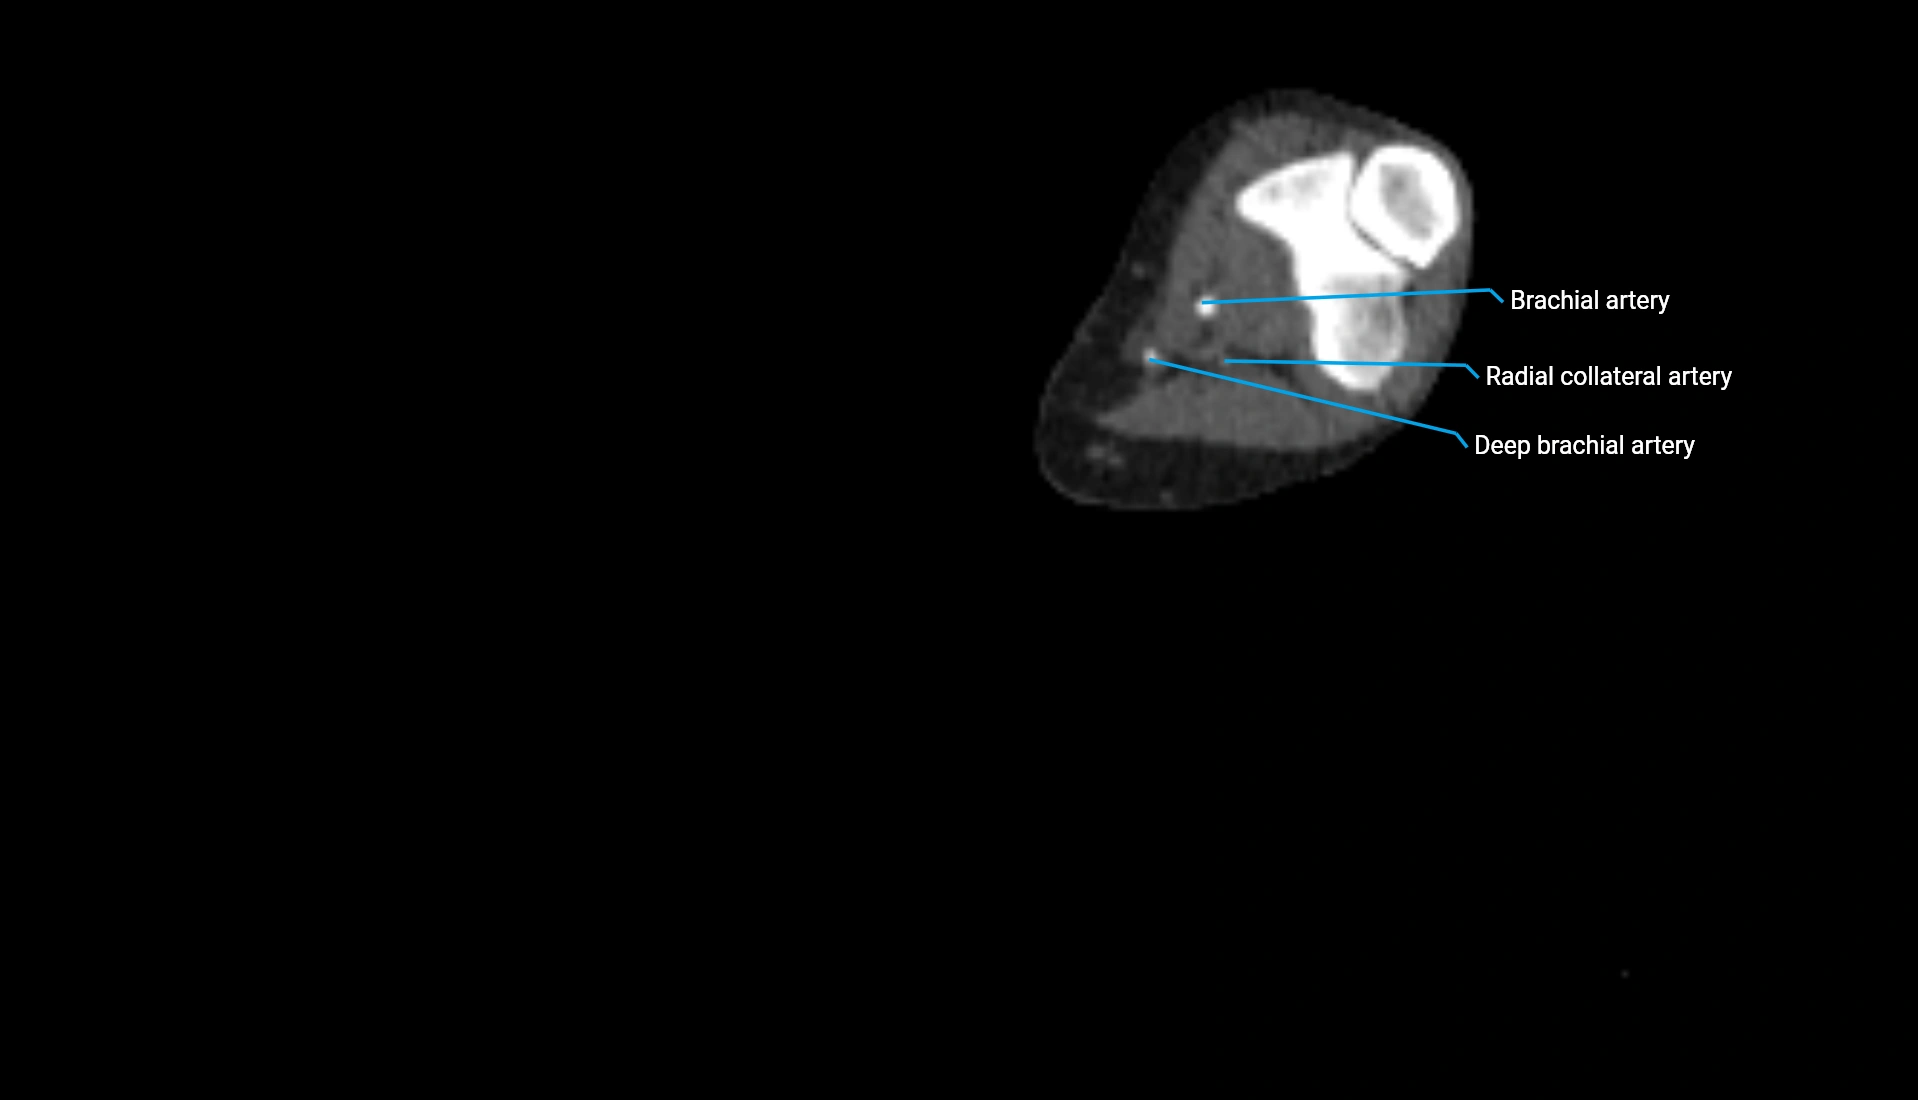

CT Appearance

Non-Contrast CT:

• Cortex: High-density, sharply defined

• Subchondral bone: Dense cancellous matrix

• Articular surface: Smooth concave contour articulating with the capitellum

• Excellent for evaluating bone integrity, alignment, and subtle fractures

Post-Contrast CT:

• Bone: No enhancement

• Joint capsule and synovium: Mild enhancement outlining the joint

• Improves contrast between soft tissues and bony margins

• Useful in detecting subtle joint abnormalities or postoperative changes